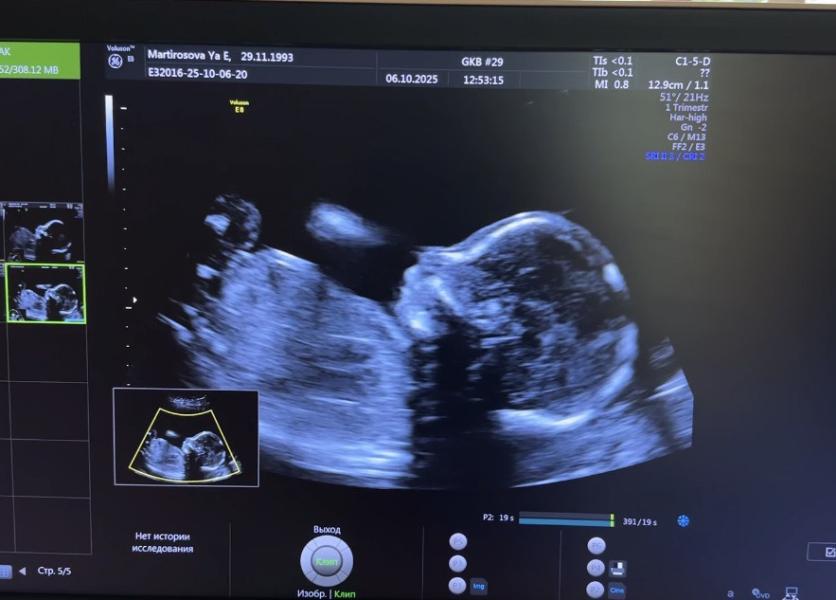

Подтвердили! Девочка!😍💝 господь, как я счастлива🥹 выхожу от врача, а меня мелкий с мамой ждали в холле. Говорю кисин, все таки девочка) и он такой на весь холл «Ооо неееет! Только не девочка! Зачем она нам нужнаааа! Зачем ее рожааать!»😂 как ваши старшие реагировали на такие новости?😁